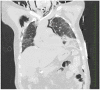

Coronavirus disease-19 caused by severe acute respiratory syndrome Corona virus-2 is characterised by wide heterogeneity in clinical presentation. The typical radiographic findings in COVID-19 include bilateral ground-glass opacities and/or consolidations predominantly affecting the lower lobes and posterior segments of lungs. Other rare abnormal radiographic findings include pneumothorax, pneumomediastinum and pneumopericardium. There has been an increased incidence of pneumomediastinum, a rare but potentially life-threatening complication during this pandemic. It may be spontaneous or secondary. Pneumomediastinum may be due to barotrauma, cytokine storm induced diffuse alveolar injury or direct viral infection of type I and type II pneumocytes. The presence of pneumomediastinum in COVID-19 patients may indicate extensive alveolar membrane destruction and those patients need close monitoring. There are no consensus guidelines in managing COVID-19 patients with pneumomediastinum. Higher mortality rates (70.58%) are reported in intubated COVID-19 patients with pneumomediastinum. The development of pneumomediastinum in COVID-19 should be considered as a poor prognostic factor.